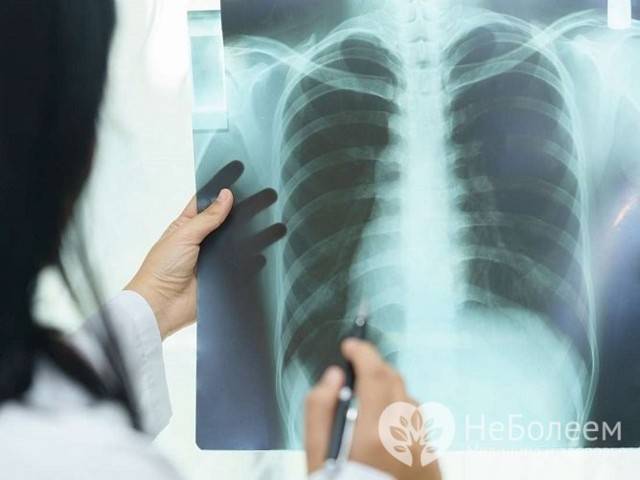

Самостоятельно по визуальным признакам определить вид пневмонии, бронхита, гриппа, туберкулеза невозможно, необходимо пройти рентген обследование. Характерные особенности легочных заболеваний:

Кроме рентгеноскопии, для определения болезней органов дыхания применяется КТ, УЗИ грудной клетки, исследование крови и мочи. А также биопсия легочной ткани.

— на рентгенограмме грудной клетки, в области легких видно затемнение, как на фото ниже:

При появлении «второй» волны заболевания необходимо обязательно обратиться к специалисту. Начинающееся воспаление в легких у взрослых и детей в такой ситуации может не проявлять себя выраженными физикальными данными. Опытные врачи и педиатры при любом подозрении назначают рентген легких. У детей может возникнуть не только пневмония, но и бактериальные осложнения в других органах, что без лечения приведет к тяжелым последствиям.

- рентгенография легких;